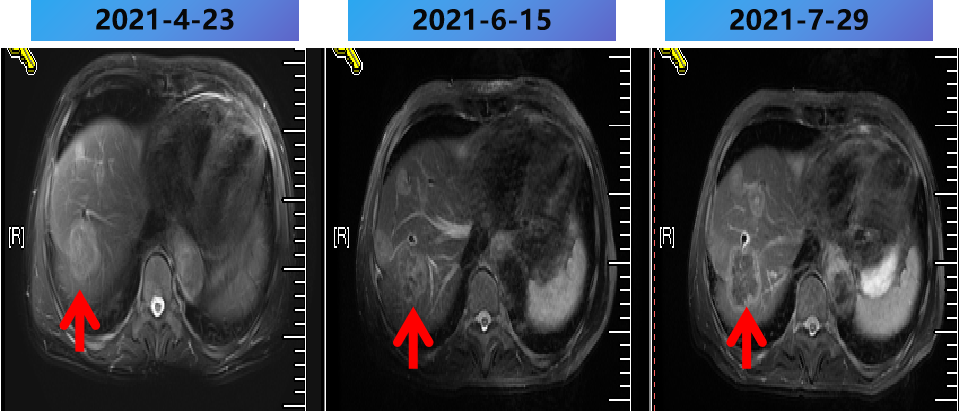

2021-2-20 (术后8m) 当地复查腹部MRI:肝脏多发转移瘤消融术后,较2021-1-5病变数目增多,体积增大。

2021-2-25至2021-7-15 更换方案为bev+伊立替康+雷替曲塞 9周期,部分病灶稳定(SD)。

2021-2-25至2021-7-25 更换方案为bev+伊立替康+雷替曲塞 9周期,部分病灶PD。